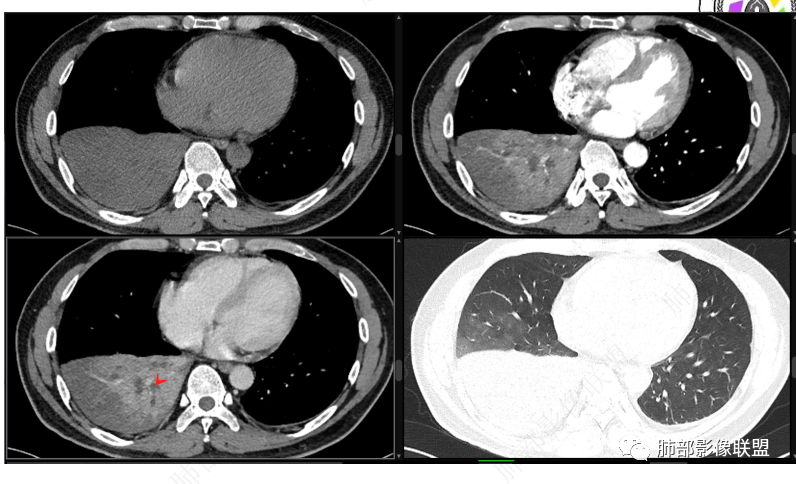

首先血管未见明显侵犯、移位,提示病灶:炎性;肿瘤:外朝内——含粘液类腺癌(肺门淋巴结转移),腔内肿瘤(鳞癌、腺癌、类癌、小细胞、粘液表皮等)

从强化看:外周密度低,强化弱

就不太符合腔内肿瘤远端不张的表现,因为外围不张——强化明显

这一例反了

按这个特点周围要考虑肿瘤组织

腔内肿瘤,远端堵塞

这个外面明显也是肿瘤部分

可能含有粘液所以这么低

我觉得粘液表皮可能要放前面

腔内

按理类癌远端密度不会这么低

而且我认为近端实变区强化与附近高密度影是否与感染有关